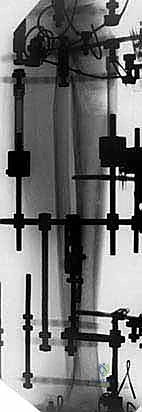

- التخطيط الإشعاعي (Pre-operative Templating): باستخدام برامج حاسوبية متقدمة والأشعة المقطعية، يقوم الدكتور هطيف بقياس الزوايا الدقيقة المطلوبة للدمج، وتحديد حجم ومقاسات المسامير النخاعية أو الشرائح المعدنية التي سيتم استخدامها.

تُجرى عملية تثبيت مفصل الكاحل والقدم (Tibiotalocalcaneal Arthrodesis) تحت التخدير النصفي أو العام، وتستغرق عادة ما بين 3 إلى 5 ساعات، نظراً لدقتها البالغة. إليك الخطوات الجراحية كما ينفذها الأستاذ الدكتور محمد هطيف وفريقه: